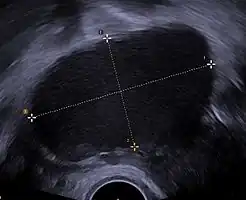

Endometrioma

| Transvaginal ultrasonography showing a 67 x 40 mm endometrioma as distinguished from other types of ovarian cysts by a somewhat grainy and not completely anechoic content. | |